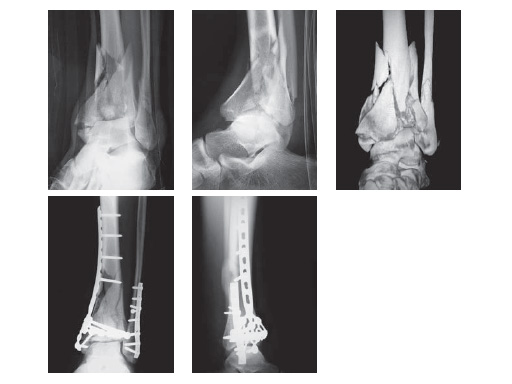

21-years-old male fell from a height of 5 m (under influence of ethanol 1.3 g/l, cannabis +)

Case provided by Patrick Croniers, Angers, France

This Pilon fracture was classified as 43-C3.2. In emergency: provisional fixation by external fixator tibia-calcaneus. ORIF on day 5 after trauma: a lateral S shaped incision for the fibula and the chaput tubercle, and a large anteromedial one, following the tibial crest and slightly curved below the medial malleolus. Large femoral distractor tibia-talus used intraoperatively. No plaster cast.